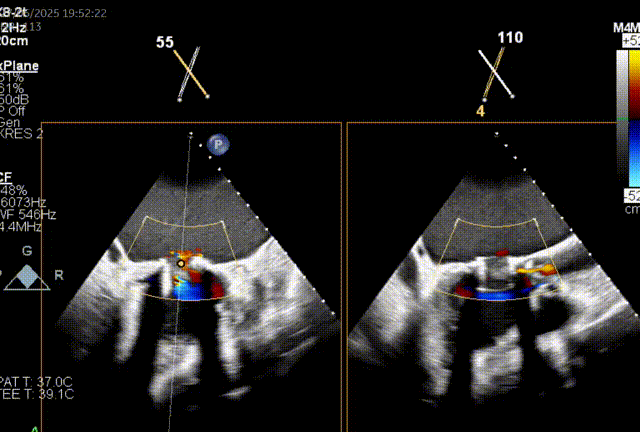

左房尺寸:长轴90.6mm,短轴79.2mm

由于二尖瓣环和主动脉瓣角度过大,若采取经心尖方式,同轴性不佳,且难以调整定位件,同样采取经房间隔方式。